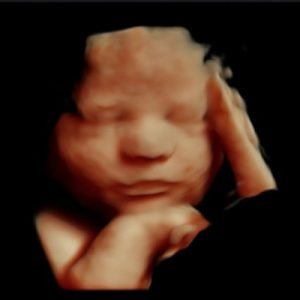

3D Υπερηχογράφημα